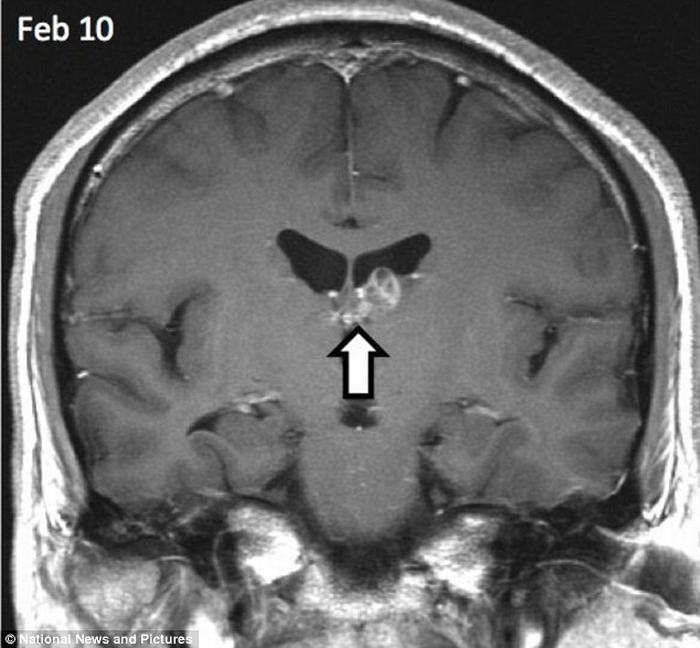

| Con sán đã ‘du lịch’ khoảng 5cm từ phía bên phải sang bên trái của não người đàn ông này trong suốt 4 năm. |